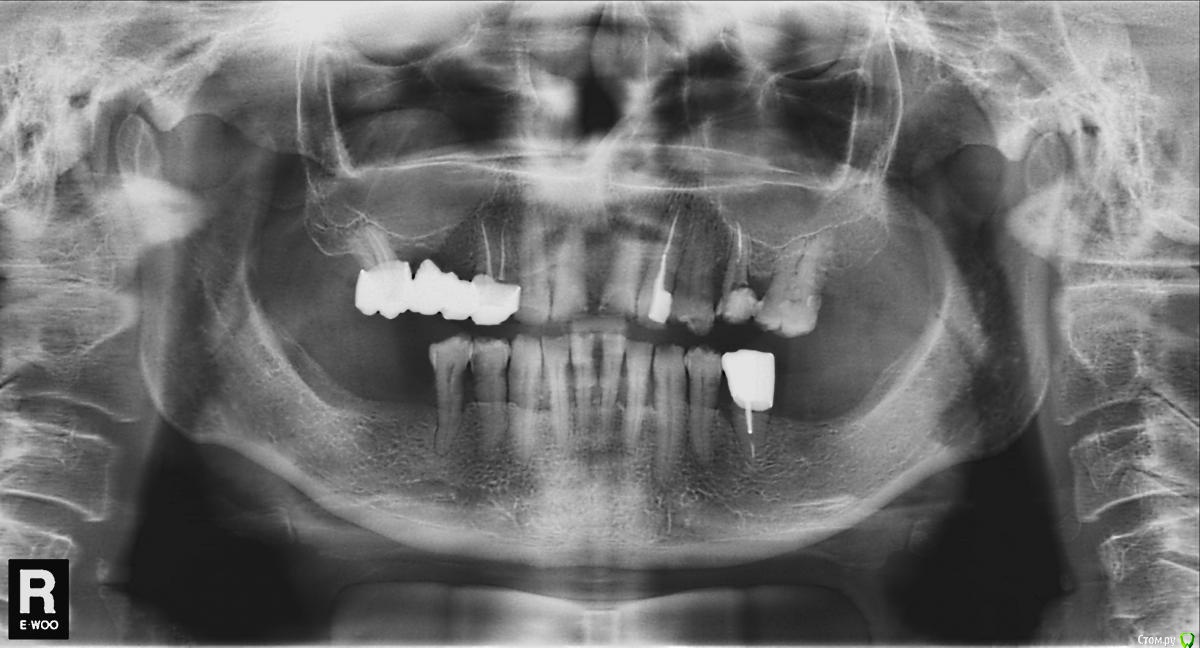

Павел7809 Опубликовано 13 сентября, 2015 Поделиться Опубликовано 13 сентября, 2015 Собственно выношу на суд орто. Интересует мнение по поводу вариантов протезирования.Имплантация - исключена - пациент беден и диабет. Для себя план лечения уже составлен, просто хотелось бы свеиже мнения послушать.... Ссылка на комментарий

Павел7809 Опубликовано 14 сентября, 2015 Автор Поделиться Опубликовано 14 сентября, 2015 забавно о пац таки созрел на импланты снизу и бюгель сверху Ссылка на комментарий

Павел7809 Опубликовано 17 сентября, 2015 Автор Поделиться Опубликовано 17 сентября, 2015 Продолжаю делится этим случаем и выкладываю на суд возможную имплантацию.1 Сначала будет удаление 5 ок с изготовлением иммедиат протеза2 Потом перевод иммедиат протеза в рентгенконтрастную модель и отправка на кт с ним( через 2 месяца после удаления)3 Имплантация по шаблону, причем на место 7 ок планирую поставить короткие альфа био....как то то так....будут какие нибуди рекомендации? Ссылка на комментарий

Bratok Опубликовано 21 сентября, 2015 Поделиться Опубликовано 21 сентября, 2015 а что с нижними резцами? кажется за ними пришла зубная смерть с щипцами ? ) Ссылка на комментарий